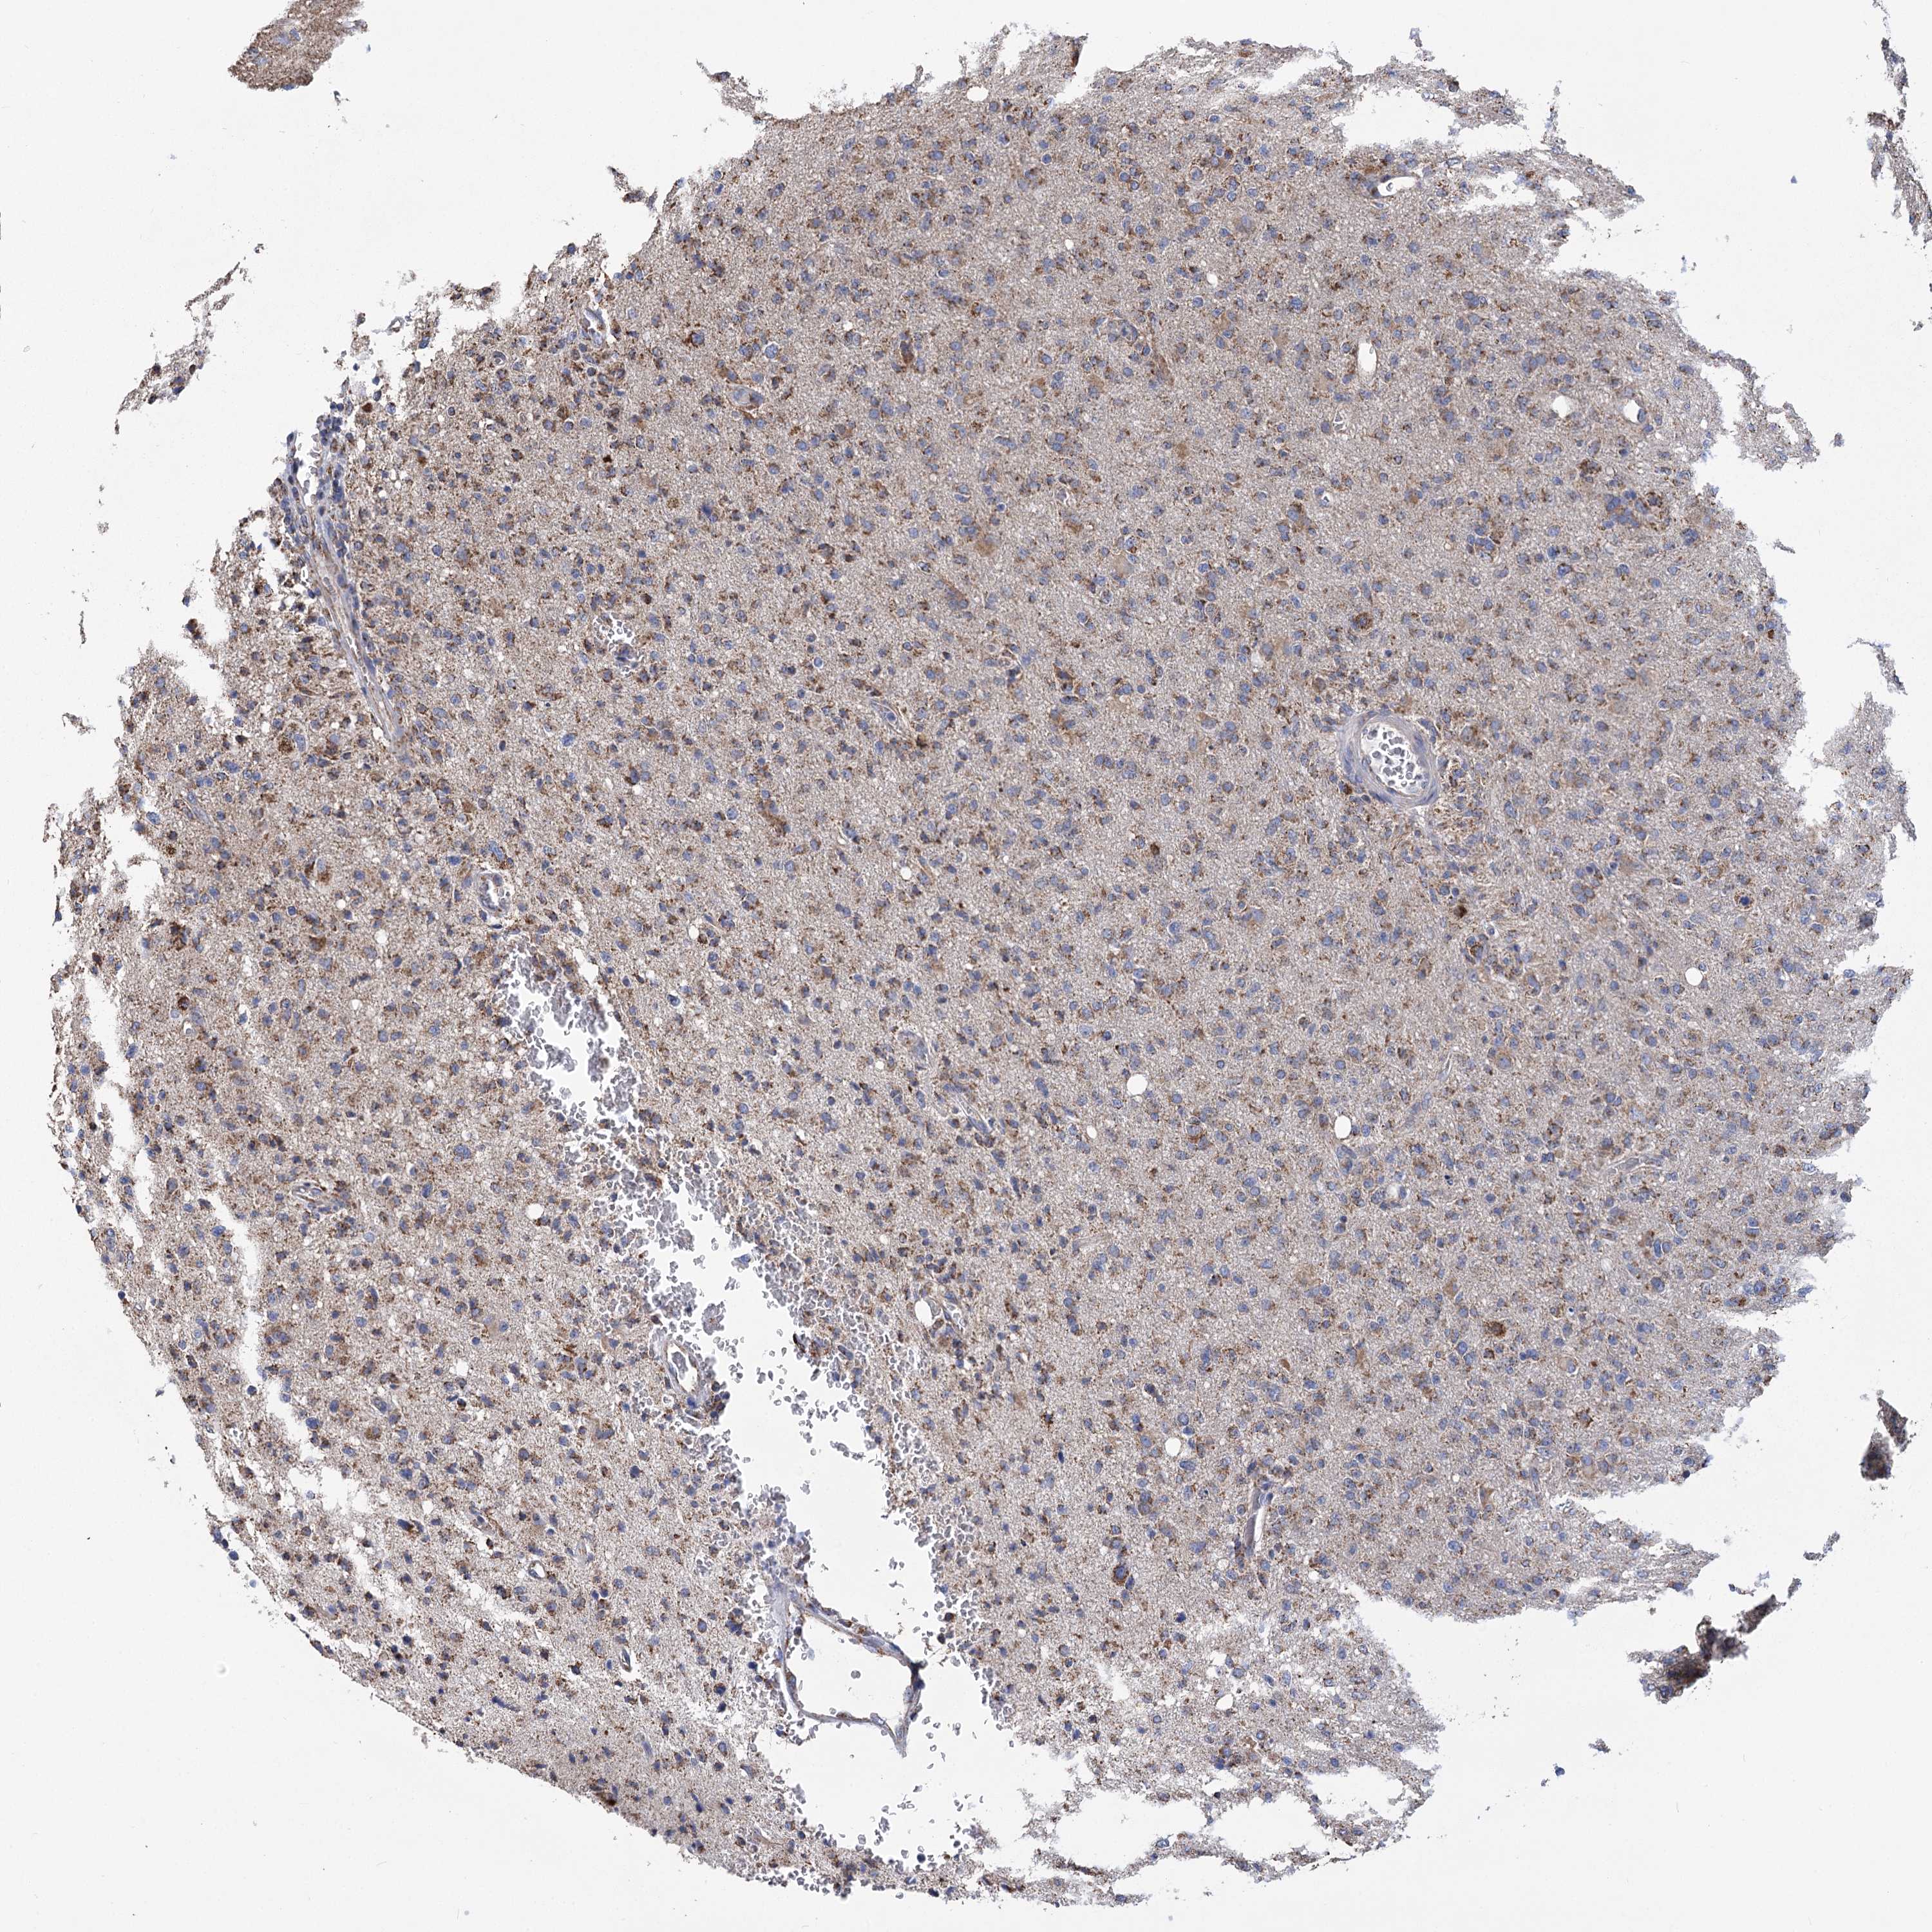

GLIOMA - Protein expressioni

A mouse-over function shows sample information and annotation data. Click on an image to view it in a full screen mode. Samples can be filtered based on level of antibody staining by selecting one or several of the following categories: high, medium, low and not detected. The assay and annotation is described here.

Note that samples used for immunohistochemistry by the Human Protein Atlas do not correspond to samples in the TCGA dataset.

Antibody stainingi

Antibody staining in the annotated cell types in the current human tissue is reported as not detected, low, medium, or high, based on conventional immunohistochemistry profiling in selected tissues. This score is based on the combination of the staining intensity and fraction of stained cells.

Each image is clickable and will lead to virtual microscopy that enables deeper exploration of all samples and also displays staining intensity scores, fraction scores and subcellular localization as well as patient and tissue information for each sample.

Antibody HPA038668

Antibody HPA038669

Staining

High

Medium

Low

Not detected

Intensity

Strong

Moderate

Weak

Negative

Quantity

>75%

75%-25%

<25%

None

Location

Nuclear

Cytoplasmic/membranous

Cytoplasmic/membranous,nuclear

Glioma, malignant, High grade

Glioma, malignant, Low grade

Glioblastoma, NOS